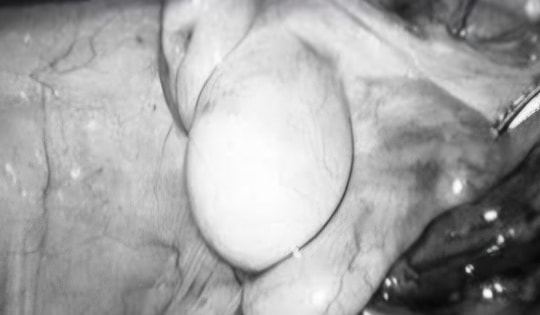

Bé trai 11 tuổi thoát nguy cơ vô sinh nhờ ca mổ nội soi hạ tinh hoàn

Ca mổ được thực hiện bằng phương pháp nội soi ổ bụng hiện đại, giúp đưa tinh hoàn về đúng vị trí trong bìu, loại bỏ nguy cơ vô sinh và ung thư tinh hoàn.